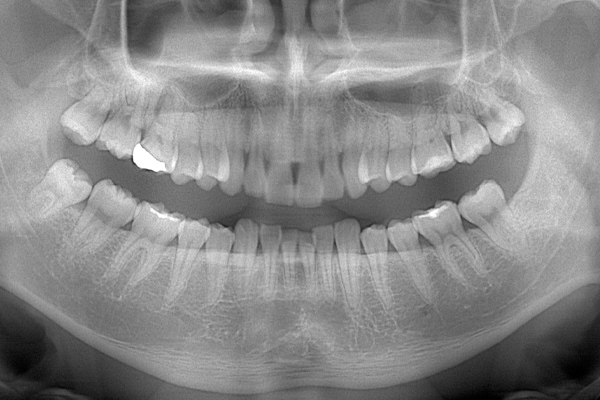

こちらは数年前の私のレントゲン写真です。右上の親知らずが斜めにはえています。お口の中には歯の頭の1部分が見えている状態です。

上顎はしっかり親知らずがはえています。下顎は右(青)はしっかりはえていますが、虫歯になっています。下顎の左(赤)は斜めにはえています。またこちらも虫歯になっています。

こちらは、下顎の親知らずが半埋伏で斜めにはえています。また、前の歯との間に虫歯をつくってしまっていたり、前の歯の根の先端の方まで骨が溶けてしまっています(智歯周囲炎)。

このように他の残さないといけない歯に悪影響を与えている親知らずに関してはなるべく早めに抜いたほうがよいです。

検査時のレントゲン写真です。

下顎の親知らずは右下のみはえています。まっすぐはえていますが、前の歯よりも低い位置にあるので、磨くのが難しそうです。舌側の歯茎がかぶっているのがみてとれます。

上顎の親知らずは頬の方を向いてはえています。こういうった親知らずはやはり磨くのがとても難しいです。